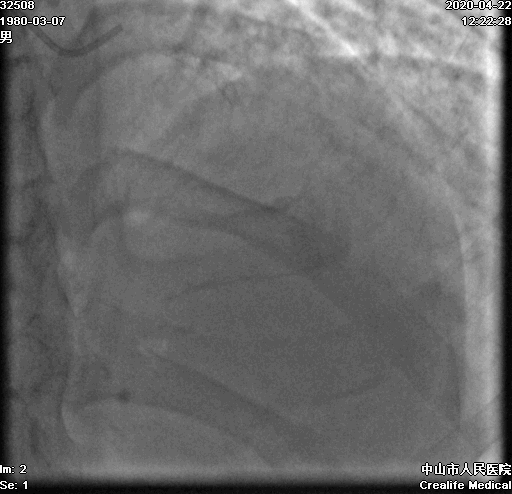

术前冠脉造影: